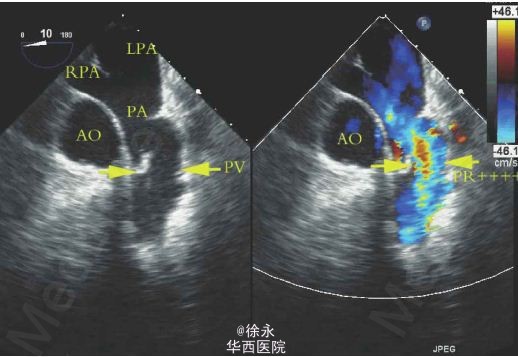

患者,女性,39 岁,25 年前因“法洛四联症”行外科治疗,近月出现活动后胸闷、心慌。超声心动图示外科术后补片下缘室水平残余分流,肺动脉瓣返流(重度)。住院期间先后行室缺残余漏封堵术+经皮导管肺动脉瓣置入术。